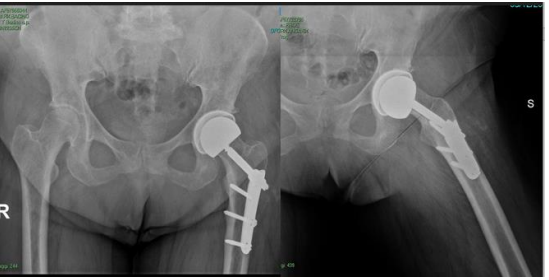

A 68-year-old female patient presented with progressive left hip pain and limited mobility, particularly during flexion and external rotation. Her medical history included a left femoral neck fracture that was treated in 1979 with a hip screw plate as well as comorbidities, such as gastroesophageal reflux disease, type 2 diabetes mellitus, ischemic heart disease, and hypertension. Imaging revealed severe left hip OA with marked joint space narrowing and femoral head deformity (Figure 1).

Figure 1: Preoperative X-ray showing the fixation devices and severe osteoarthritis.

The patient initially underwent conservative treatment, including pain management and physiotherapy. However, her symptoms worsened, which led to the decision to perform THA. A preparatory attempt to remove the internal fixation hardware was unsuccessful due to severe osseointegration. Because the position of the femoral screw prevented the placement of any stem, including that of a simple resurfacing prosthesis, the use of a custom-made implant was necessary (Figure 2).

mobility. At her September 2023 follow-up, she was walking independently without aids, with a range of motion (ROM) of 0–90° flexion and 0–30° abduction. By December 2023, the patient reported no pain, with ROM exceeding 90° and unrestricted rotation. At her latest follow-up in March 2024, she demonstrated excellent functional outcomes, including pain-free ambulation, independent stair climbing, and the resumption of daily activities (Figure 7). Occasional mild discomfort related to weather changes was her only residual symptom.

Figure 7: One-year postoperative follow-up showing proper prosthesis positioning and no interference with the fixation devices.